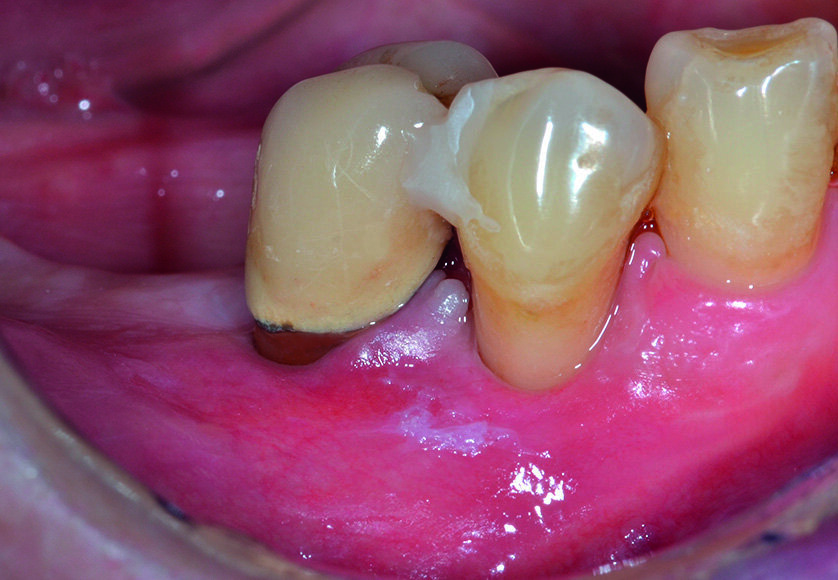

Al momento del controllo a 8 mesi vengono esaminate le condizioni dei tessuti parodontali marginali e si effettua una radiografia endorale periapicale, che evidenzia la completa risoluzione del difetto intraosseo (Figg. 17, 18). Incidentalmente, in occasione della scopertura dell’impianto precedentemente inserito, si sceglie di constatare de visu la rigenerazione ottenuta intorno all’ elemento 4.5: al sollevamento del lembo è possibile apprezzare la completa risoluzione del difetto intraosseo circonferenziale, a conferma di quanto già emerso dal controllo radiografico (Figg. 19, 21). Dopo aver esposto la testa dell’impianto in zona 4.6 si rimuove la vite di copertura, che viene sostituita con un healing abutment di adeguate dimensioni (Figg. 22, 23).

Al termine di un adeguato periodo di guarigione, necessario alla completa maturazione e al condizionamento dei tessuti molli, è possibile constatare come l’emergenza implantare sia adesso circondata da una banda di gengiva aderente adeguata per ampiezza e spessore, condizioni che favoriranno il mantenimento dello stato di salute nel medio e lungo termine (Figg. 26, 27). Una protesi definitiva in metallo - ceramica viene cementata sull’impianto in zona 4.6; il successivo controllo radiografico e il sondaggio parodontale confermano una sostanziale stabilità dei risultati ottenuti sia a livello dell’elemento 4.5 che dell’ impianto in zona 4,6 (Figg. 28-30).